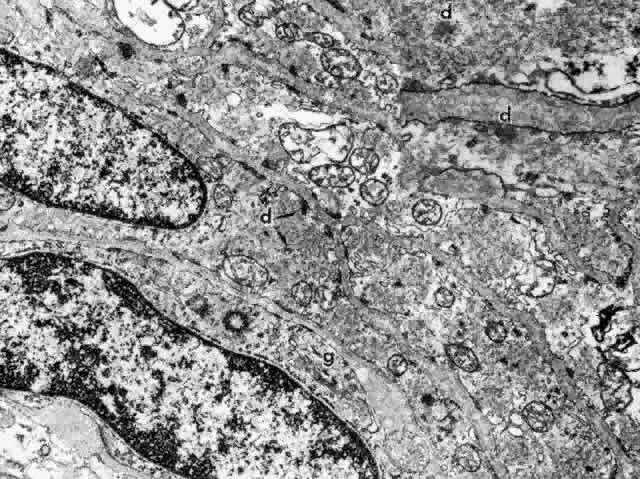

CILIARY BODY STROMA

The stroma of the ciliary body contains all the usual components of extracellular matrix including collagens, elastic system fibers, and small matrix molecules such as proteoglycans. The cellular components are melanocytes, fibroblasts, blood vessels, and nerves, besides the large quantity of smooth muscle comprising the bulk of this tissue. In the first one and one-half decades the nonvascular connective tissue in the ciliary processes is scanty, resulting in the thin, underdeveloped appearance of the juvenile ciliary processes (Fig. 28A). Their vessels are primarily fenestrated capillaries and veins, forming plexi (see later section on blood supply). The subepithelial tissue in the processes and plicae becomes very much thickened by collagenous and hyaline material with aging (Fig. 28B and C), extending down to the ciliary muscle itself. In the deeper stroma, capillaries are usually not fenestrated and show intermittent pericytes outside the endothelial cell layer, surrounded by basement membrane that merges with that of the endothelial cells (Fig. 29). The ciliary processes are essentially vascular structures and do not contain extensions of the ciliary muscle, so the muscle has the same thickness under the processes as under the ciliary valleys (Fig. 30).

Fig. 29. Intermittent pericyte (P) coverage and lack of fenestrae in the endothelial cell wall characterize capillaries of the deeper stroma in the pars plicata. Basement membrane (BM) is multilayered. Fibroblast (FB) has active rough endoplasmic reticulum and a large cisterna with granular material. A small clump of elastic system microfibrils is seen at its upper edge (arrow). (X 20,900)